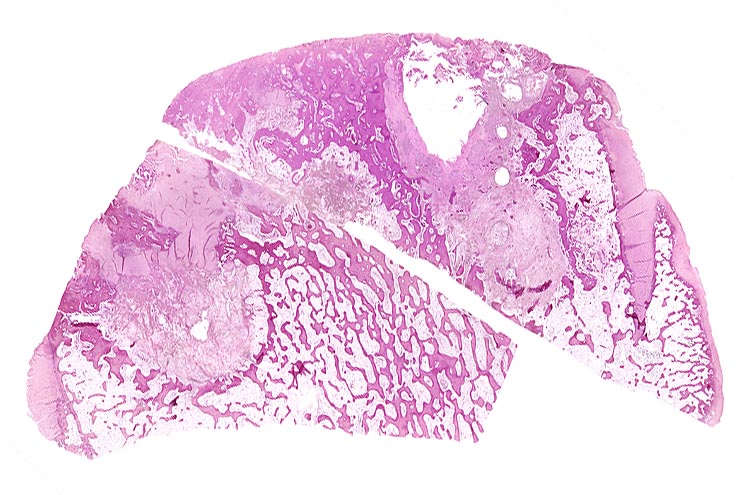

PathoPic – image database / PathoPic ID 4602 - Coxarthrose

Coxarthrose

Knochen, Femurkopf

Zusammengehörige topographische Übersichtspräparate eines Schenkelkopfes mit Arthrose, von zwei verschiedenen Paraffinblöcken stammend. Die Präparate passen mit ihren Schnittflächen in etwa zusammen. Im Randbereich erhaltener Gelenkknorpel. Randosteophyt. Geröllzysten.

74-jährige leicht adipöse Patientin mit Anlaufschmerz, belastungsabhängigem Schmerz und zunehmender Versteifung im Hüftgelenk. Im Röntgenbild des Hüftgelenks zeigen sich eine Gelenkspaltverschmälerung, subchondrale Osteolysen, Usuren und randständige Osteophyten.